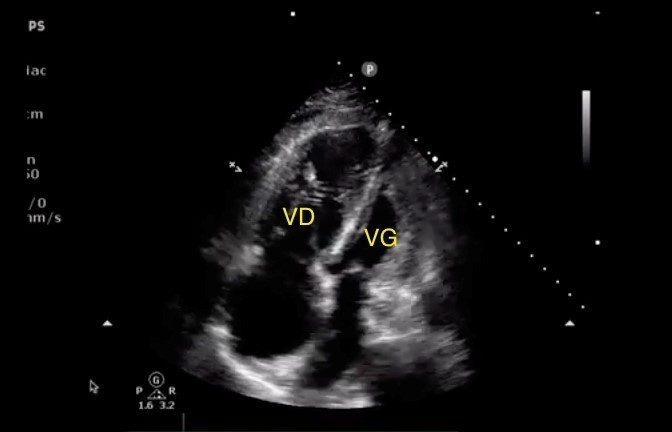

Voici les coupes de l’échographie cardiaque.

Coupe parasternale petit axe :

Coupe apicale 4 cavités :

Coupe parasternale grand axe :

* VD = ventricule droit, VG = ventricule gauche.

Les autres données de l’examen sont : une fonction ventriculaire gauche conservée, un débit cardiaque abaissé, une pression dans l’oreillette droite élevée avec une augmentation des pressions artérielles pulmonaires systoliques.

Aspect de cœur pulmonaire aigu (CPA)

Pas d’épanchement péricardique sur les coupes d’échocardiographie transthoracique (ETT)

Images évocatrices de CPA.

Caractéristiques d’un CPA :

– augmentation de la pression artérielle pulmonaire systolique (PAPS), évaluée sur l’insuffisance tricuspide ;

– dilatation du ventricule droit (VD) [rapport VD/VG > 0,9] que l’on voit ici ;

– inversion de la courbure septale (bombement septal vers la gauche en proto-diastole) que l’on voit ici ;

– puis dysfonction VD.